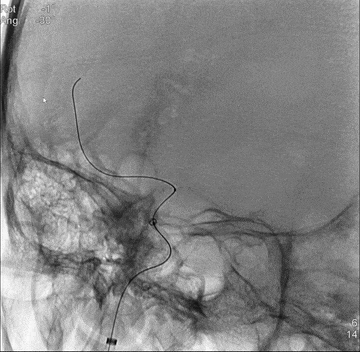

急诊血管内介入治疗

同轴技术将6F长鞘(Cook,90cm)头端送至右侧颈内动脉C1远端,泥鳅导丝导引6F中间管至海绵窦段,微导丝导引微导管通过闭塞,并行进至M2,微导管造影证实位于真腔后,送入并释放一取栓支架(Trevo 4*20mm),造影示闭塞再通,抽拉结合取栓一次,后造影见闭塞部分再通,局部管腔明显狭窄,大脑前动脉未见再通。

以前文所述方法再次释放取栓支架,以Solumbra技术取栓一次,闭塞再通,右侧大脑中动脉和双侧大脑前动脉恢复血流,但见一小血栓逃逸至右侧A1段远端。

此为两次取栓取出的多量血栓。

微导丝微导管配合超选至左侧大脑前动脉A2段,此时造影发现,右侧A1血栓进一步逃逸至左侧大脑前动脉A4段分支,考虑到绝大部分原严重缺血组织已恢复供血,远端血管闭塞取栓出血风险高,结束手术。

术后即刻DSA平板CT未见颅内出血征象。